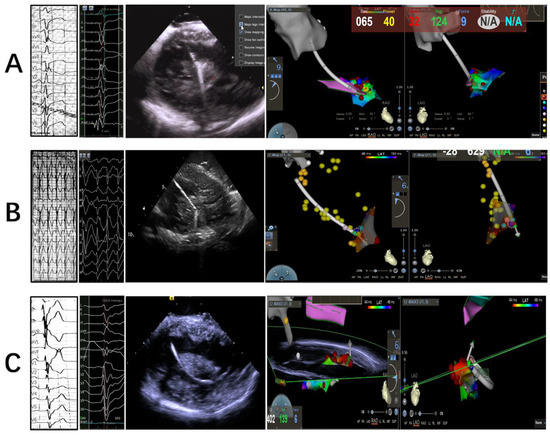

2.2. Electrophysiology Study, Mapping and Ablation

2.2.1. Intracardiac Echocardiography

2.2.2. Mapping and Ablation